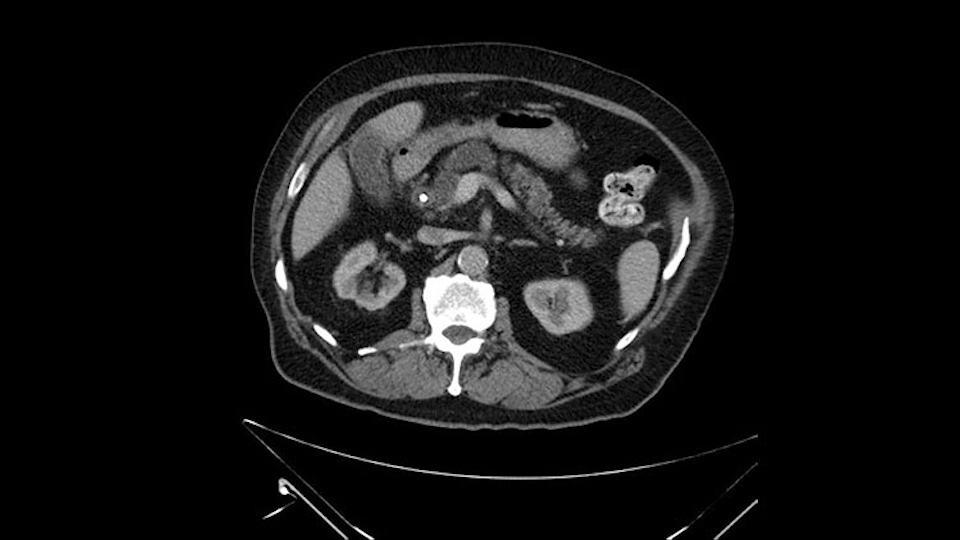

The next item that I would look at: the issue would be the vessels and usually start at the portal vein, watch the portal vein, follow it down, down-down-down to the neck of the pancreas - which is here - and there’s no impingement by tumor, which is great. The SMV and the splenic vein, which is here. The splenic vein junction is normal, which is great.

Then look at the first jejunal branch - which is this thing here - this little branch which goes under the SMA. It’s something that we’ve just started appreciating over the past few years and the reason for that is: there’s two or three small branches that come out of the uncinate into the the first jejunal and it’s a fairly inevitable part of the operation where there’s some bleeding. As long as you’re cognizant of what’s happening, it’s no reason to panic and that kind of bleeding will eventually stop or can be stopped but it’s not easy because these little vessels are fragile from the uncinate to the first jejunal. So I do focus on that and it’s pretty consistent I’d say 9 times out of 10, people have that first jejunal.

Then either through the coronal or the axial, I’ll do both. Look at the SMA -which is here- I had already looked at it and I don’t see any involvement. There’s the SMA with a nice fat plane between the SMA and the tumor. Over here you can see on the axial, there’s the SMA. Everything on the right side of the SMA has got some nice black around it, which is fat, which means probably no tumor [no tumor, no tumor]. Follow it up to the origin, coming off the aorta. So those are the two technical things that I worry about: the SMA and the SMV.

The initial hepatic flexure mobilization and the Kocher procedure is then going to enable me to understand the uncinate process of this patient, which should not be a problem, again. But the initial pictures had shown a degree of touching. I would not even say involvement or abutment; a degree of touching with the superior mesenteric vein. So that would give me an early chance to assess how the superior mesenteric vein is in this patient. So this would be the initial slowing down moment.

To plan a pancreatoduodenectomy, we start by reviewing the vascular anatomy, especially the origin of the celiac trunk, here, in front of the aorta, looking for any evidence of stenosis. In addition, we look at the origin of the superior mesenteric artery, to look for any branches, and any replaced right hepatic arteries coming from the superior mesenteric artery; which does occur in about 12% of the population.

The next thing we always evaluate, although we do not expect invasion to the portal veins in this case, we must always trace the path of the portal vein, in both directions, from top to bottom. The splenoportal confluence and the superior mesenteric vein, which in this case does not appear to be compromised.